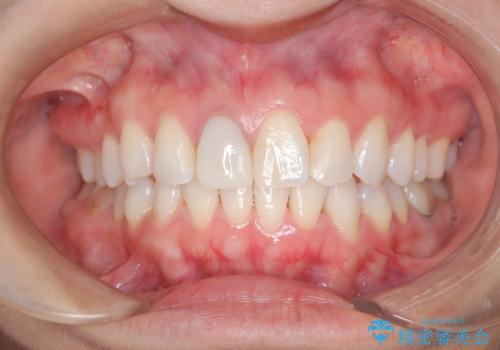

- 前歯のガタつき、変色を主訴に来院された患者様です。術前診査のCT撮影にて、変色した前歯の根の先に病巣があることが判明しました。そこで、マウスピースによる矯正治療と、前歯の根管治療、かぶせ物のやり直し治療を並行して行いました。